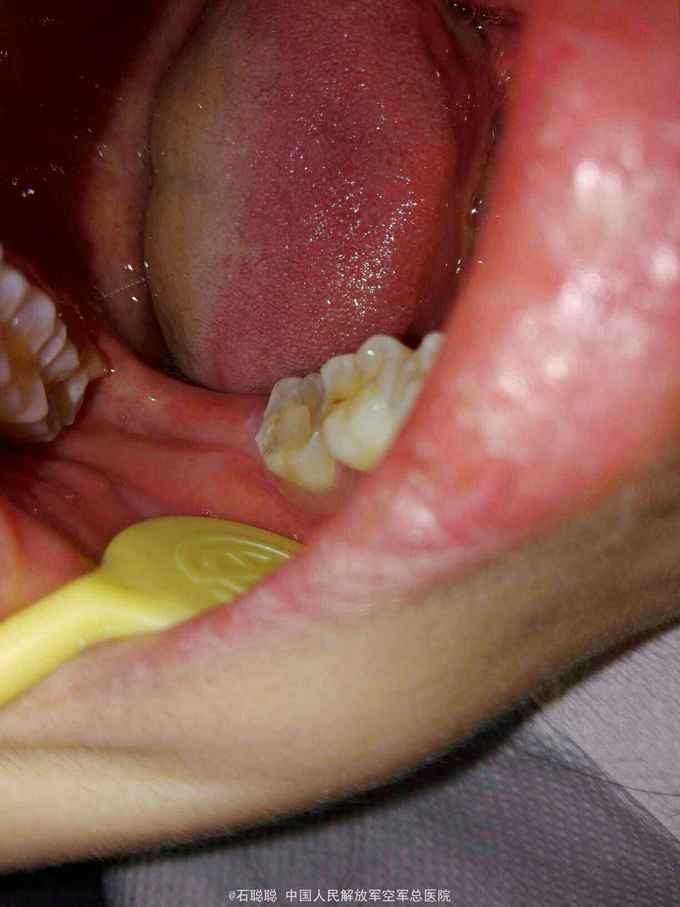

右下7全瓷嵌体冠修复

检查:47合面见白色暂封物完整在位,近中、远中、颊侧、舌侧壁厚度>2mm。咬合紧。叩痛-,无明显松动,牙龈未见明显异常,牙周探诊深度2mm。 根尖片:47根管内高密度充填影像,恰填,牙周膜、根尖区及根分叉未见异常

诊断:47牙体缺损 治疗计划:47全瓷嵌体冠修复 处置:47去除暂封,磷酸锌垫底,光固化覆合树脂充填,预备全瓷嵌体冠,取模,比色3M2,制作临时冠,调合,磨光,粘固 一周后复诊: 检查:临时冠完整在位,无松动,叩痛- 处置:去除47临时冠,试戴全瓷嵌体冠,调合,抛光,U200粘接 医嘱:勿用患牙咀嚼脆骨、坚果等过硬食物 口腔卫生宣教:巴斯刷牙法,牙线使用方法 不适复诊

讨论:这是常一例规的后牙根管治疗后要求修复的病历,患牙的对合略有伸长,咬合紧,尽管将对合做了降合处理,仍会降低龈合距离,削弱全冠的固位力,幸运的是47的四个轴壁均完整并且高度、厚度能满足制作嵌体冠的需要,可以利用髓腔制备固位形,明显改善了固位不足的状态。嵌体预备要点要满足轴壁无倒凹,有2-5度的合方外展,与牙冠就位道一致。